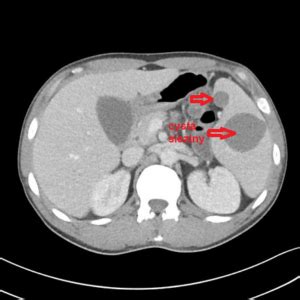

Embolizácia aneuryzmy slezinovej artérie (MUDr. Alan Lumsden)